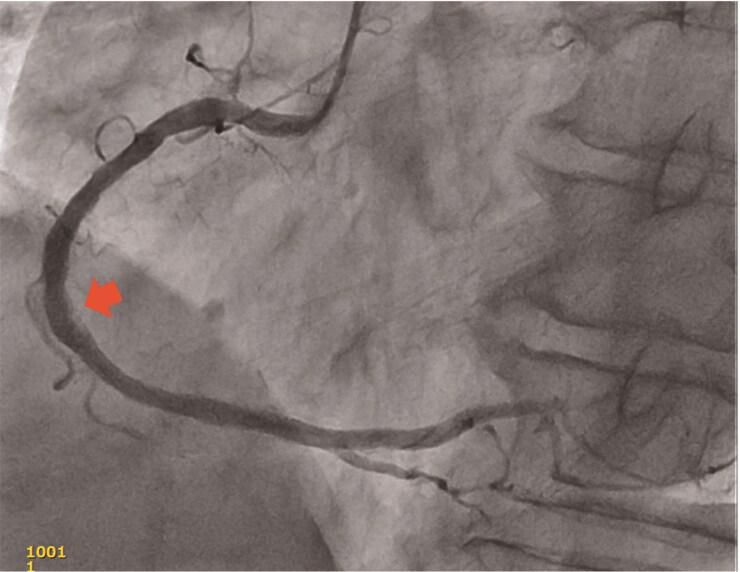

A 71-year-old was referred to our hospital because of typical effort angina pectoris. Diagnostic coronary angiography identified significant severe stenosis in the middle segment of right coronary artery (RCA). In the primary percutaneous coronary intervention (PCI), intravascular ultrasound visualized the eccentric protruding high echoic structure with irregular surface indicating CNs. Percutaneous coronary intervention was successfully performed with rotational atherectomy (RA). However, one year after the PCI, effort angina was recurrent. The patient experienced recurrent restenosis three times, even after repeated PCI using RA and treatment with drug coating balloon. In the fourth PCI, we tried guide wire penetration through the CNs before RA to reduce the more amount of CNs tissue; finally, good patency was achieved. At last, follow-up angiography after final PCI showed no in-stent restenosis.

We report a case of a patient who required repeated revascularization to a severe stenotic lesion with CNs in the middle segment of the RCA. Rotational atherectomy after wire penetration into the CNs was effective to avoid a malignant cycle of restenosis.

一名71岁患者因典型劳力性心绞痛转诊至我院。诊断性冠状动脉造影显示右冠状动脉(RCA)中段存在严重的重度狭窄。在初次经皮冠状动脉介入治疗(PCI)中,血管内超声显示出偏心突出的高回声结构,表面不规则,提示为CNs。采用旋磨术(RA)成功完成了经皮冠状动脉介入治疗。然而,PCI术后一年,劳力性心绞痛复发。即使在使用RA重复进行PCI并采用药物涂层球囊治疗后,患者仍三次出现再狭窄复发。在第四次PCI中,我们在RA之前尝试将导丝穿过CNs以减少更多的CNs组织;最终实现了良好的通畅。最后,末次PCI后的随访血管造影显示无支架内再狭窄。

我们报告了一例患者,其RCA中段伴有CNs的严重狭窄病变需要反复进行血运重建。导丝穿透CNs后进行旋磨术有效地避免了再狭窄的恶性循环。